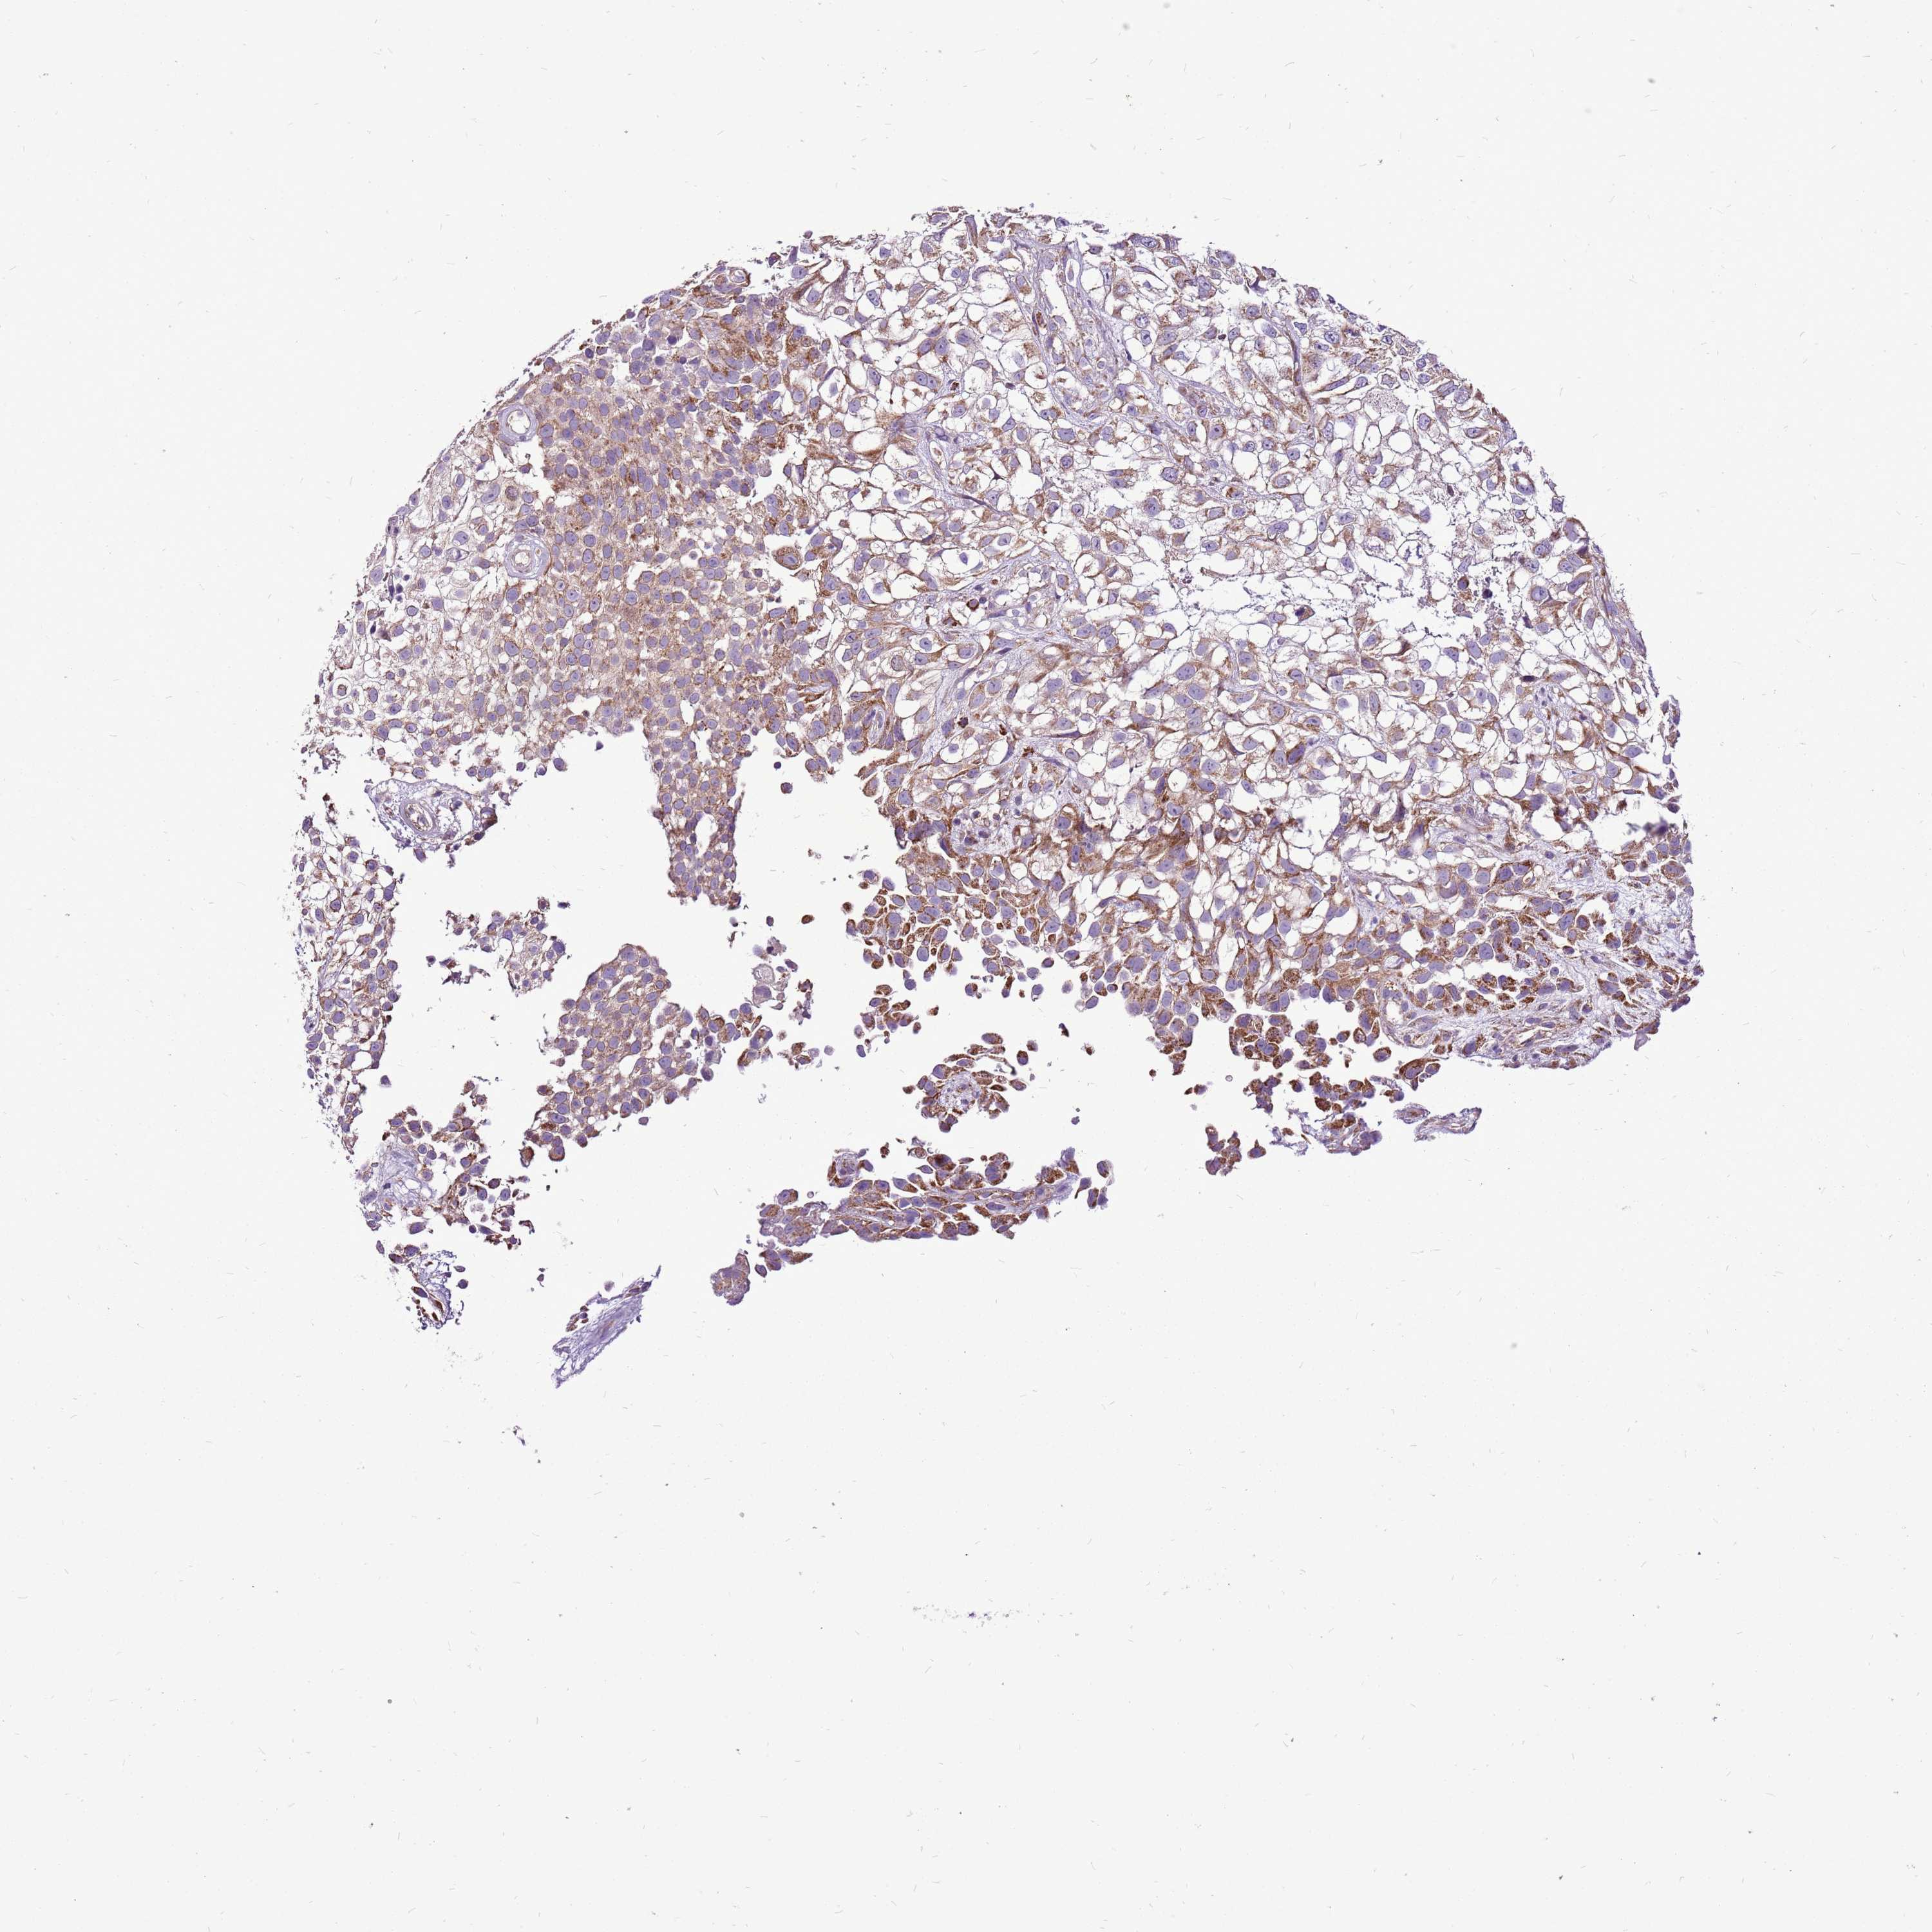

UROTHELIAL CANCER - Protein expressioni

A mouse-over function shows sample information and annotation data. Click on an image to view it in a full screen mode. Samples can be filtered based on level of antibody staining by selecting one or several of the following categories: high, medium, low and not detected. The assay and annotation is described here.

Antibody stainingi

Antibody staining in the annotated cell types in the current human tissue is reported as not detected, low, medium, or high, based on conventional immunohistochemistry profiling in selected tissues. This score is based on the combination of the staining intensity and fraction of stained cells.

Each image is clickable and will lead to virtual microscopy that enables deeper exploration of all samples and also displays staining intensity scores, fraction scores and subcellular localization as well as patient and tissue information for each sample.

Antibody HPA043252

Antibody HPA048492

Urothelial carcinoma, High grade

Urothelial carcinoma, Low grade